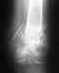

с 4го мес наступаю в полный вес на больную ногу. меня беспокоит то, что на снимках в 5 мес край осколка диафиза сильней очерчен на снимке, чем на снимке за 4й месяц.на сколько я знаю, при сращении края должны наоборт становиться более размытыми. не свидетельствует ли это о том, что возможно увеличение нагрузок привело к разрушению костной мозоли? перелом был полный, разлом произошел приблизительно на линии метаэпифиза. да и мыщелки не целы. и еще вопрос. мне на 1-2мм уменьшили расстояние между мыщелковыми стержнями и стержнями, проведенными через ср.треть бедра. появилвсь боль в латеральном мыщелке, которая через 3 дня ищезла. я вообще не могу понять, как такое воздействие может не привести к разрушению еще слабой костной мозоли. опорности ноги еще нет. не могли бы вы мне что-то объяснить? волнуюсь жутко, так как лечусь уже 3.5 года. снимки приложить пока что для меня сложно.